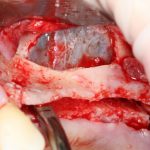

Откроем область операции и посмотрим, что там:

Вроде как, всё неплохо. Наверное, можно поставить имплантаты?